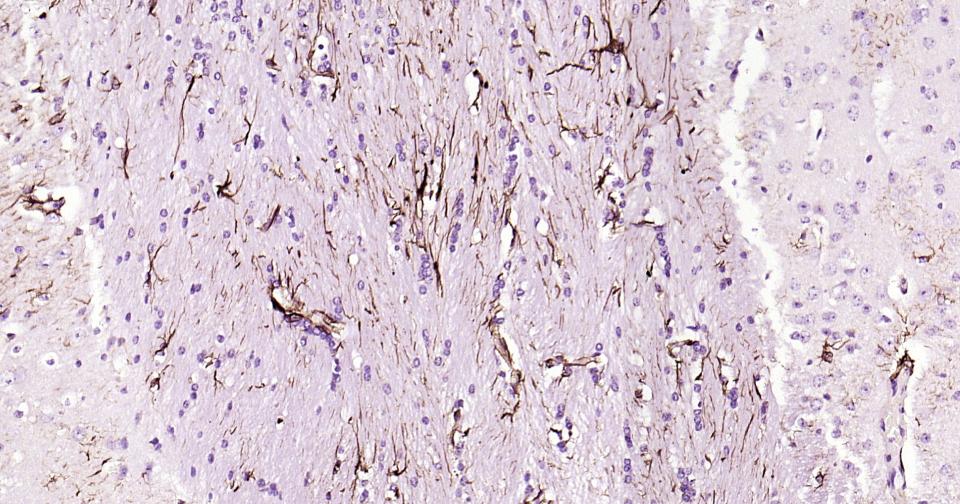

Paraformaldehyde-fixed, paraffin embedded Human Cerebellum; Antigen retrieval by boiling in sodium citrate buffer (pH6.0) for 15 min; Antibody incubation with GFAP Monoclonal Antibody, Unconjugated(bsm-42001M-Bio) at 1:200 overnight at 4°C, followed by co

Paraformaldehyde-fixed, paraffin embedded Rat Cerebellum; Antigen retrieval by boiling in sodium citrate buffer (pH6.0) for 15 min; Antibody incubation with GFAP Monoclonal Antibody, Unconjugated(bsm-42001M-Bio) at 1:200 overnight at 4°C, followed by conj

Paraformaldehyde-fixed, paraffin embedded Mouse Cerebrum; Antigen retrieval by boiling in sodium citrate buffer (pH6.0) for 15 min; Antibody incubation with GFAP Monoclonal Antibody, Unconjugated(bsm-42001M-Bio) at 1:200 overnight at 4°C, followed by conj

Paraformaldehyde-fixed, paraffin embedded Rat Cerebrum; Antigen retrieval by boiling in sodium citrate buffer (pH6.0) for 15 min; Antibody incubation with GFAP Monoclonal Antibody, Unconjugated(bsm-42001M-Bio) at 1:200 overnight at 4°C, followed by conjug